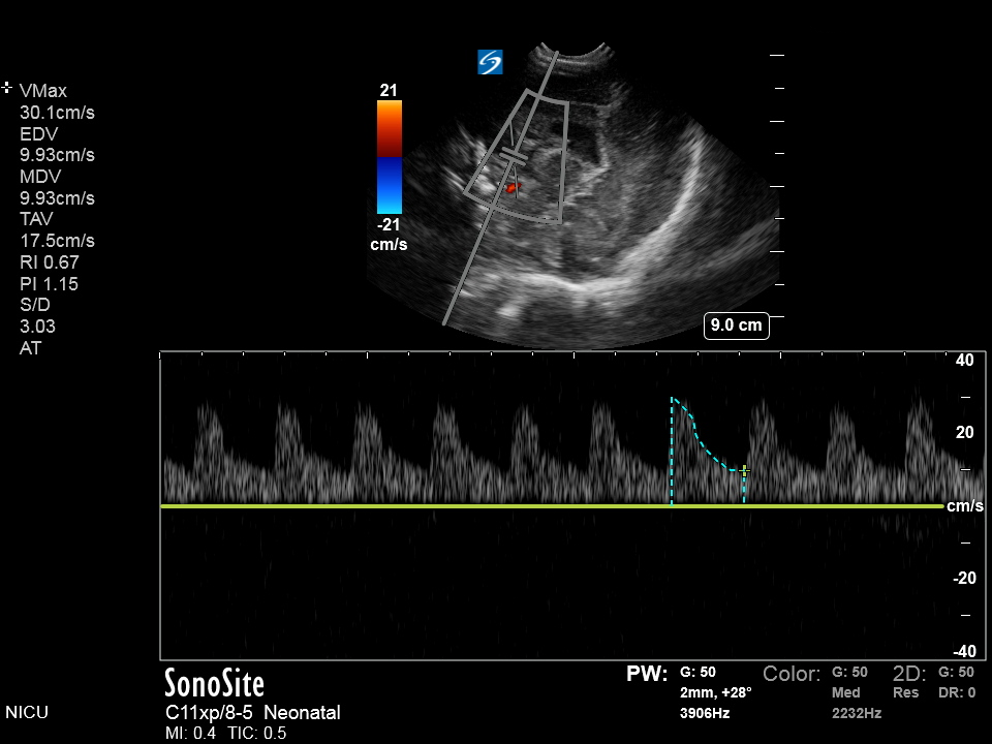

Neonatology Hydrocephalus Compression Test A Image